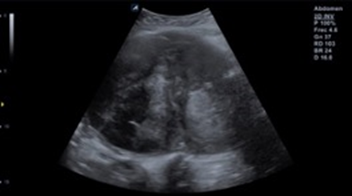

Magnetic resonance imaging 11.30.2021 uterus with loss of morphology, with the presence of an intramural fibroid of 16x11x16 cm, with areas of hyaline degeneration (Image 2) (Image 3).

Image 2 Associated with areas of necrosis and approximate volume of 820.41 cc (c).